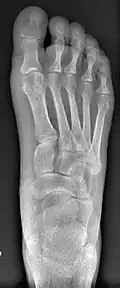

- For recurrence correction after osteotomy procedure (Fig. 8)

Late deformity recurrence can happen after osteotomy (bone-breaking) procedures because osteotomy surgeries do not specifically stabilize first metatarsal bone.